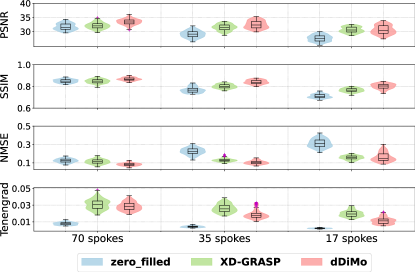

Quantitative results comparing reconstruction methods at different undersampling levels (70, 35, and 17 spokes) are summarized in Table 2. dDiMo consistently achieves the highest PSNR and overall image similarity with respect to the reference across all undersampling levels, outperforming both Zero-filled and XD-GRASP. While XD-GRASP achieves the highest Tenengrad score at all undersampling levels, it performs worse in terms of overall image similarity. This is attributed to the presence of noise in XD-GRASP reconstructions, which leads to inflated Tenengrad scores, as also observed in Figure 7. Violin plots in Figure 8 provide a visual comparison of the distributions of PSNR, SSIM, NMSE, and Tenengrad metrics for different acceleration settings. dDiMo exhibits narrower distributions and fewer outliers compared to Zero-filled and XD-GRASP in most cases, reflecting its stable and robust performance.